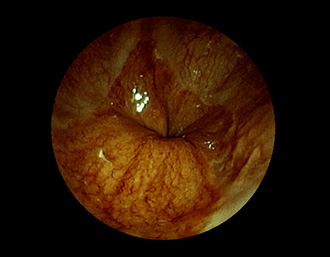

症例1:胃潰瘍(37才、男性)

①胃潰瘍(Stage A1)

健診:胃レントゲン検査で、胃角部ニッシェを指摘され当院受診。

胃角部小弯に、深くて大きな、大きさ約10mmの胃潰瘍(stage 1)

があり、潰瘍底は一部白苔はみ出しを認める。エソメプラゾールマグネシウム水和物投薬で治療開始しました。

(FICE+インジゴカルミン散布画像)